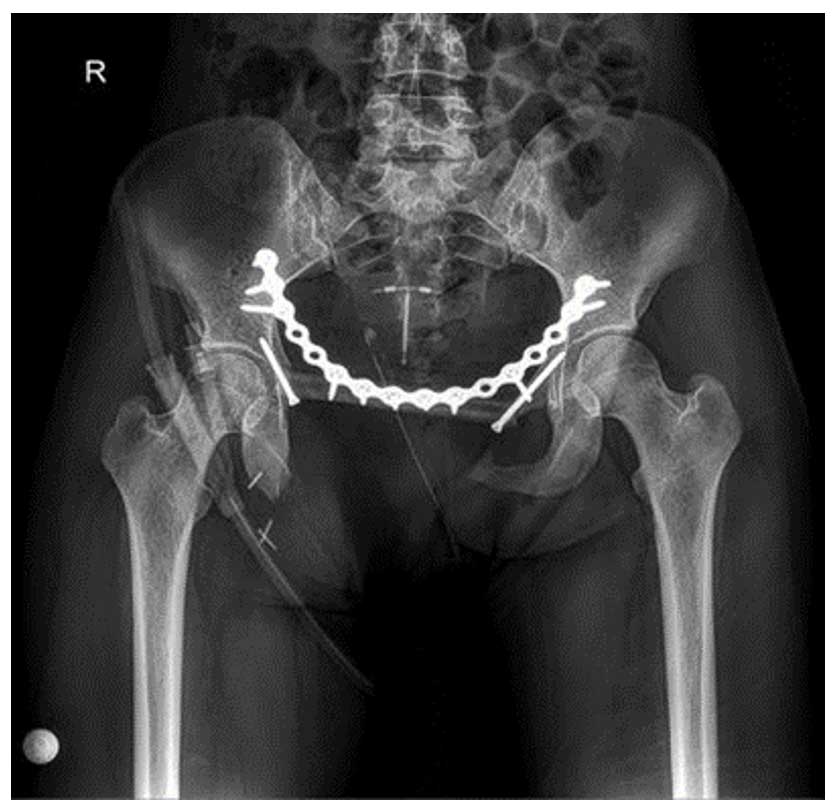

Ameliyat Sonrası: Rezeksiyon sonrası fibula ve plak/vida ile yapılan rekonstrüksiyon görülmekte.